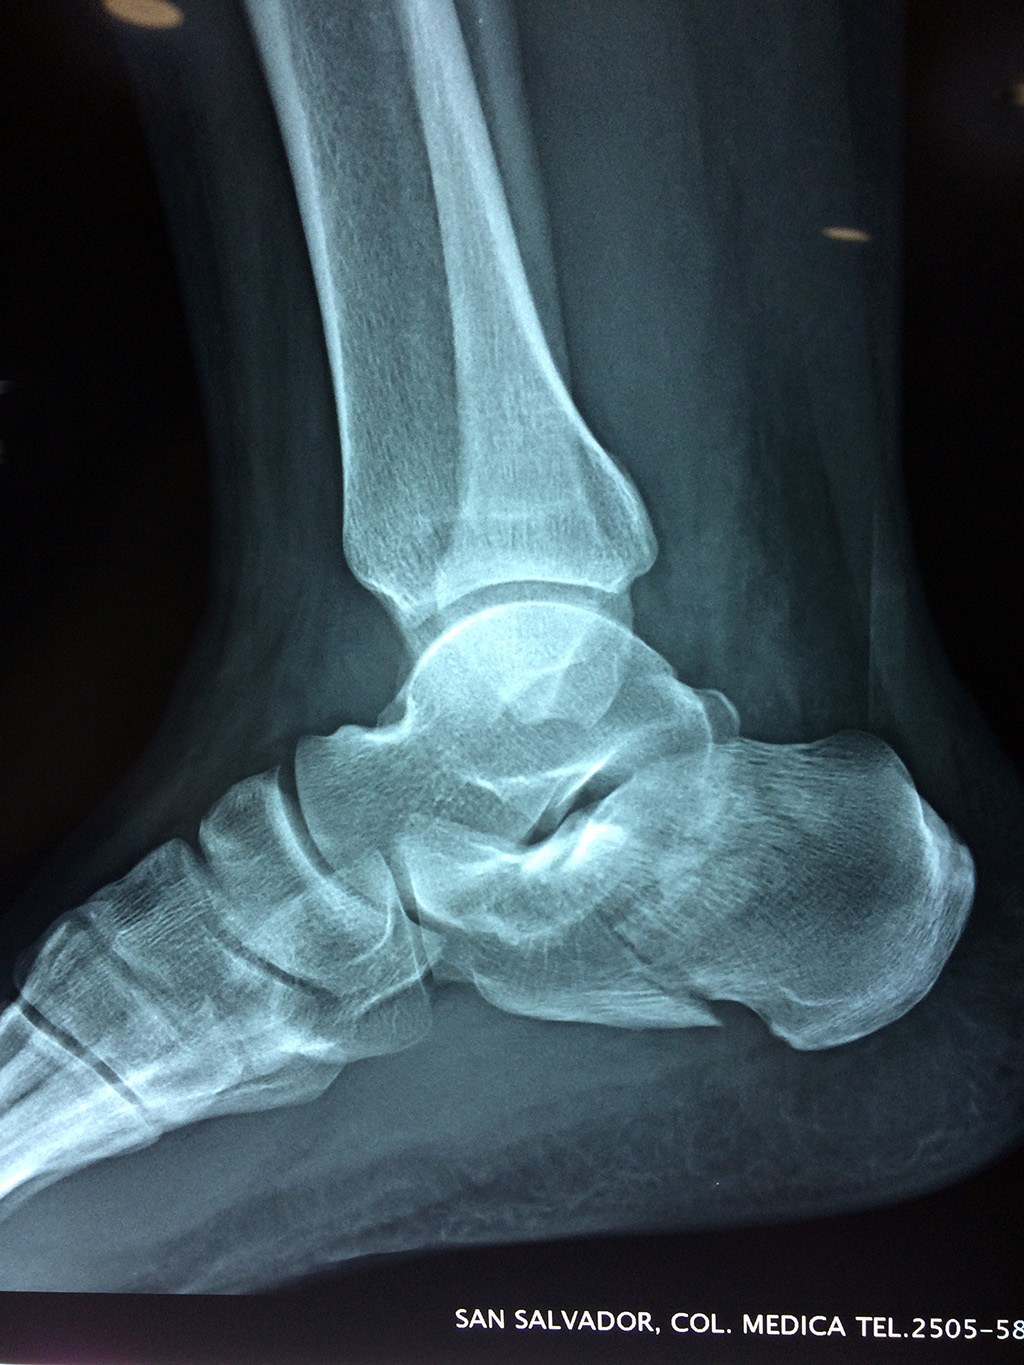

Este hueso constituye el talón del pie. Se encuentra en la parte inferior de la primera fila del tarso. Se articula con el astrágalo por arriba y con el cuboides por delante. Constituye el primer punto de apoyo del pie durante la marcha, situándose en una de las zonas peor irrigadas del cuerpo y protegido plantarmente por la almohadilla plantar de tejido adiposo, con función amortiguadora.

En su cara posterior recibe la inserción del tendón más plantar, implicada en diversas enfermedades como la fascitis o el espolón calcáneo. La posición del calcáneo en relación al astrágalo (articulación subastragalina) y al suelo determinan la posición de retropié en varo, en valgo o neutra.

Los retropiés varos y sobre todo, los retropiés valgos, son responsables de distintas enfermedades del aparato locomotor y contribuyen a que aparezcan alteraciones de la marcha normal fisiológica, con consecuencias clínicas importantes (dolor, sobrecargas, aplanamiento, fatiga muscular, juanetes, etc.) tanto a nivel de pie como a nivel del miembro inferior.

De todo esto se deriva que su posicionamiento espacial es muy importante para contribuir a una marcha correcta y a la salud del resto del conjunto articular del pie.